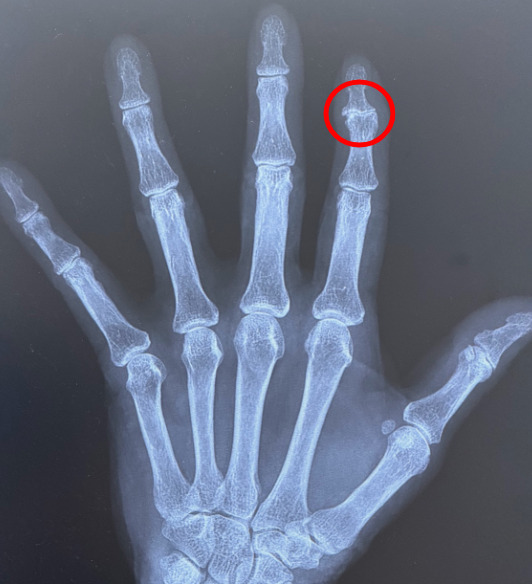

レントゲン(正面・側面)でDIP関節の関節裂隙の狭小化や消失、関節周囲の骨棘形成がみられます。DIP関節に結節をつくるものをヘバーデン結節、PIP(近位指節間)関節に同様の所見をつくるものをブシャール結節と呼びます。びらん性関節症(erosive OA)に進行した場合には、DIP関節で「カモメが翼を広げたような形(gull-wing appearance)」、PIP関節で「ノコギリ歯状(saw-tooth)」といった特徴的なX線像を示します。